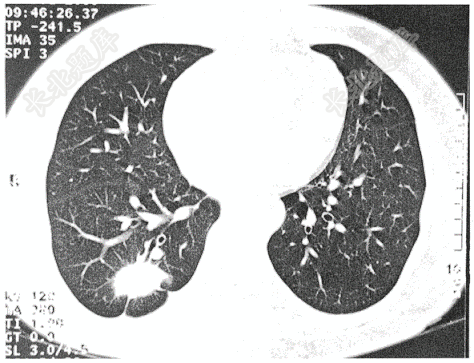

- 单项选择题男性患者,因体检胸片发现右下肺病变入院,既往体健,有粉尘接触史。否认吸烟史。查体无异常。最可能诊断是( )

A、结核球

B、机化性肺炎

C、炎性假瘤

D、周围型肺癌

E、球形肺炎